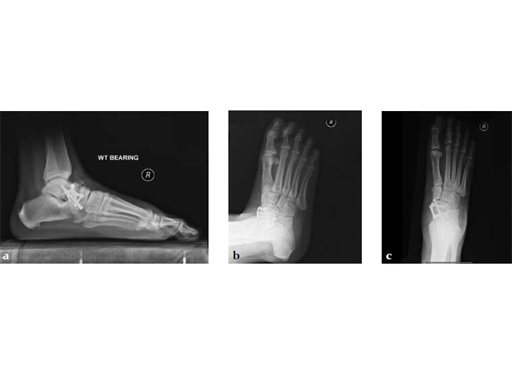

Case 5: First TMT, straight fusion and TMT fusion plates

A 46-year-old obese woman with coronary artery disease had sustained a Lisfranc injury while performing an exercise program. She was unable to weight bear and used an electric scooter.

In an effort to restore her ability to exercise and taking into consideration her body weight and upper extremity weakness, a decision was made to use the variable angle locking compression plate. These postoperative x-rays were obtained at 3 months, one month after beginning weight bearing. The patients pain was reduced and she was able to resume a progressive exercise program after 4 months following surgery.

Case provided by Michael Castro, Scottsdale, Arizona